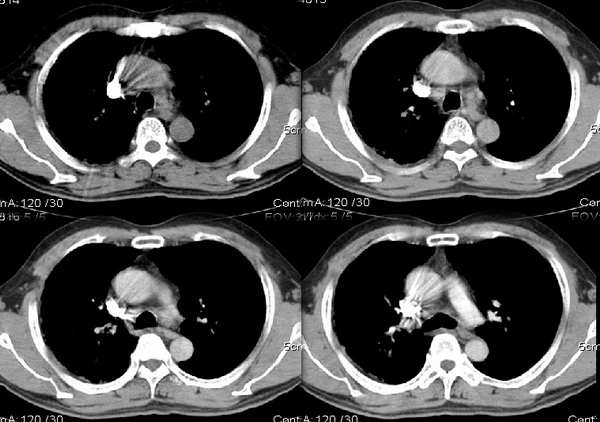

男54岁咳嗽咯痰2w,外院胸片示“右上大叶性肺炎抗炎治疗后部分吸收

右肺上叶少量间质炎性表现,结合病史为大叶性肺炎未吸收完表现。

结合病史,右上肺病变考虑炎症,继续抗炎治疗后复查;

该病人54岁,胸膜下可见多个类圆形透亮影,是不是还要考虑慢性/弥漫性肺疾病可能?

请问右中叶支气管开口旁不强化结节影是什么?

右上叶支气管变窄.ca?